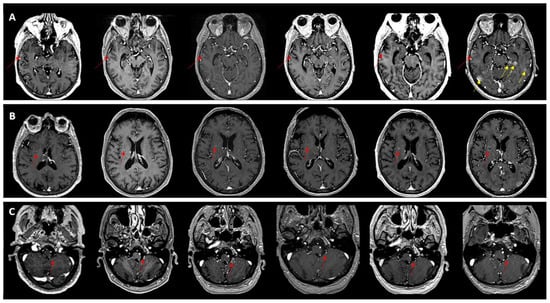

Temporal Dynamics and Heterogeneity in Brain Metastases: A Single-Center Retrospective Analysis of Vulnerabilities in Current MRI Surveillance Practices

by Claudia Tocilă-Mătășel, Sorin Marian Dudea and Gheorghe Iana

Medicina 2026, 62(1), 187; https://doi.org/10.3390/medicina62010187 (registering DOI) - 16 Jan 2026

Background and Objectives: Brain metastases frequently evolve over time in multiple waves, especially in patients with prolonged survival. Despite repeated imaging and targeted therapies, lesion-level continuity is fragmented in clinical practice, as follow-up is typically limited to pairwise MRI comparisons. The aim of the study is to assess the ability of routine narrative MRI follow-up reports to preserve longitudinal lesion identity and to reconstruct a coherent trajectory of disease evolution. Materials and Methods: We conducted a single-center, retrospective, observational study of all brain MRI examinations performed between June 2024 and June 2025 (n = 731 scans, 616 patients). All imaging reviews and longitudinal lesion tracking were performed by one board-certified neuroradiologist. Adult patients with confirmed brain metastases and at least three MRI examinations (including external studies) were included. We assessed the concordance of routine narrative MRI follow-up reports against a longitudinal review of all available MRIs and treatment timelines, which served as the reference standard. Lesion identity was considered preserved when reports explicitly recognized and linked lesions across time points, and lost when identity was omitted or ambiguous in at least one report. Results: The final cohort comprised 73 patients (477 tracked lesions). More than half of monitored lesions disappeared (42.9%) or evolved into post-treatment sequelae (9.9%), and were omitted from narrative reports, limiting retrospective recognition without prior imaging. The ability of routine reports to preserve lesion identity declined as cases became more complex. Concordance was higher in uniform evolution patterns (≈60%) but dropped to 18.2% in mixed evolution. A similar decline was seen with sequential metastatic waves, defined as new metastases appearing at distinct time points: 65.2% (1 wave), 46.7% (2 waves), 18.2% (3 waves), and complete loss of continuity when >3 waves occurred. Conclusions: Routine narrative MRI follow-up reports generally provide adequate information in simple cases with uniform lesion behavior, but tend to lose critical details as disease trajectories become more complex, particularly in heterogeneous or multi-wave disease. Even when individual lesions are identified across examinations, documentation remains fragmented and reflects only a snapshot of the disease course rather than an integrated longitudinal perspective. These findings highlight a critical vulnerability in current follow-up practices. Improving lesion-level continuity, potentially through AI-assisted tools, may enhance the accuracy, consistency, and clinical utility of MRI surveillance in patients with brain metastases. Full article

Figure 1